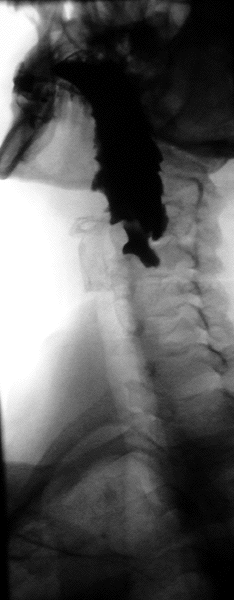

Normal barium swallow fluoroscopic image, showing the ingested barium sulfate being induced down the oesophagus by peristalsis. | |

A barium swallow study is also known as a barium esophagram and needs little if any preparations for the study of the larynx, pharynx, and esophagus when studied alone.[11][12]

A thick barium mixture is swallowed in supine position and fluoroscopic images of the swallowing process are made. Then several swallows of a thin barium mixture are taken and the passage is recorded by fluoroscopy and standard radiographs. The procedure is repeated several times with the examination table tilted at various angles. A total of 350–450 mL of barium is swallowed during the process.[14][15] Normally, 90% of ingested fluid should have passed into the stomach after 15 seconds.[16]